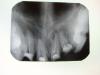

Fred Опубликовано 23 июля, 2008 Поделиться Опубликовано 23 июля, 2008 Фред, опыт работы большой? Практический? Может, поделишься профессиональными секретами? Потому что эти инструменты вынуть нельзя. Мне так кажется. Разве что выпилить. Как под вкладки-и турбиной. В медиальном каналонаполнитель( пружина, которая держит ещё 2 инструмента), в дистальном вообще полный полотенец. Скажи, что можно сделать? Нет, опыт небольшой, но такие обломки получить - это радость эндодонтиста. УЗ тонким вокруг торца инструмента рубить столько, пока он не выскочит. Правда, без микроскопа шансы куда хуже, но с микроскопом у меня есть правило - если видишь обломок, обязательно его вынешь.А как Вы работали, опишите поподробнее, может смогу понять, почему это у Вам не получилось. Вот данная коллекция файлов, сломанных мною, куда более сложная, тем не менее ... Хотя без перфы и не обошлось .... http://www.100mat.ru/ubb/photo/images/12163202672.jpg http://www.100mat.ru/ubb/photo/images/12163202783.jpg Ссылка на комментарий

Гость Vini Vidi Vici Опубликовано 23 июля, 2008 Поделиться Опубликовано 23 июля, 2008 Фред, судя по снимку-нёбный овер. Ничего? А инструмент вынул замечательно! Я бы не смогла. А чем запломбировал? Ссылка на комментарий

Korabahtoff Опубликовано 24 июля, 2008 Поделиться Опубликовано 24 июля, 2008 А какие Ваши индикации к удалению? 1. Мне кажется, что если и нет там перфо, то до него рукой подать.2. Человек провозился столько и ни один не достал.3. Каково последующее ортопедическое лечение? Но чтоб твёрдо сказать, мне ещё и в рот посмотреть охота. Меня смущает ещё и то, что не вижу я пломбировочного материала. Тогда к чему там обломок каналонаполнителя... Вопросы есть ещё, конечно... Но только после того, как в рот посмотрел бы. Ссылка на комментарий